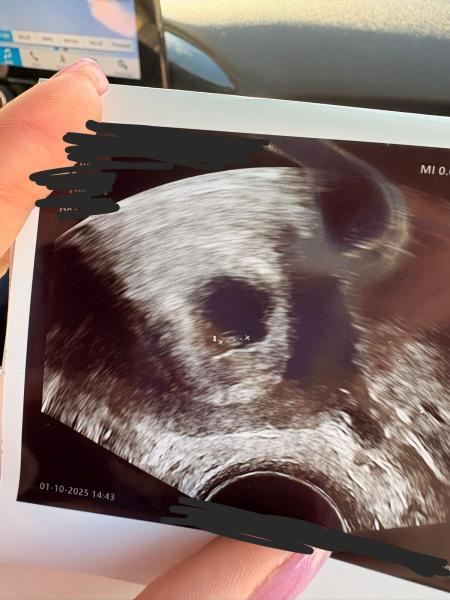

Hallo an Alle, heute hatte ich den zweiten Ultraschall und man hat eine kleine Fruchthöhle gesehen. (da wo der kleine Pfeil hin zeigt) Dazu auch noch etwas anderes. Hier mal ein Foto. Die Ärztin meinte das könnte Blut von einer Einnistungsblutung sein.  Beim ersten Ultraschall hatte man nur eine aufgebaute Schleimhaut gesehen. Daheim war jetzt tatsächlich ein bisschen Blut am Papier... vermute das es vom Ultraschall kommt.  Jetzt die Frage: sah das bei einer von euch auch so aus? Und wie war dann der Verlauf?  Gerne mit Bild! ☺️ Die Ärztin meinte es ist noch alles offen... das hat sie auch mehrmals wiederholt... das hat mich ein bisschen verunsichert aber ich denke das hat sie so nicht gemeint... denn sie hat ja recht 🙈 Hab nächsten Freitag wieder einen Termin. Ich denke und hoffe das man dann mehr erkennen kann ☺️ Liebe Grüße

Bild zu Erster Ultraschall - Kinderwunsch - was tun, um schwanger zu werden?